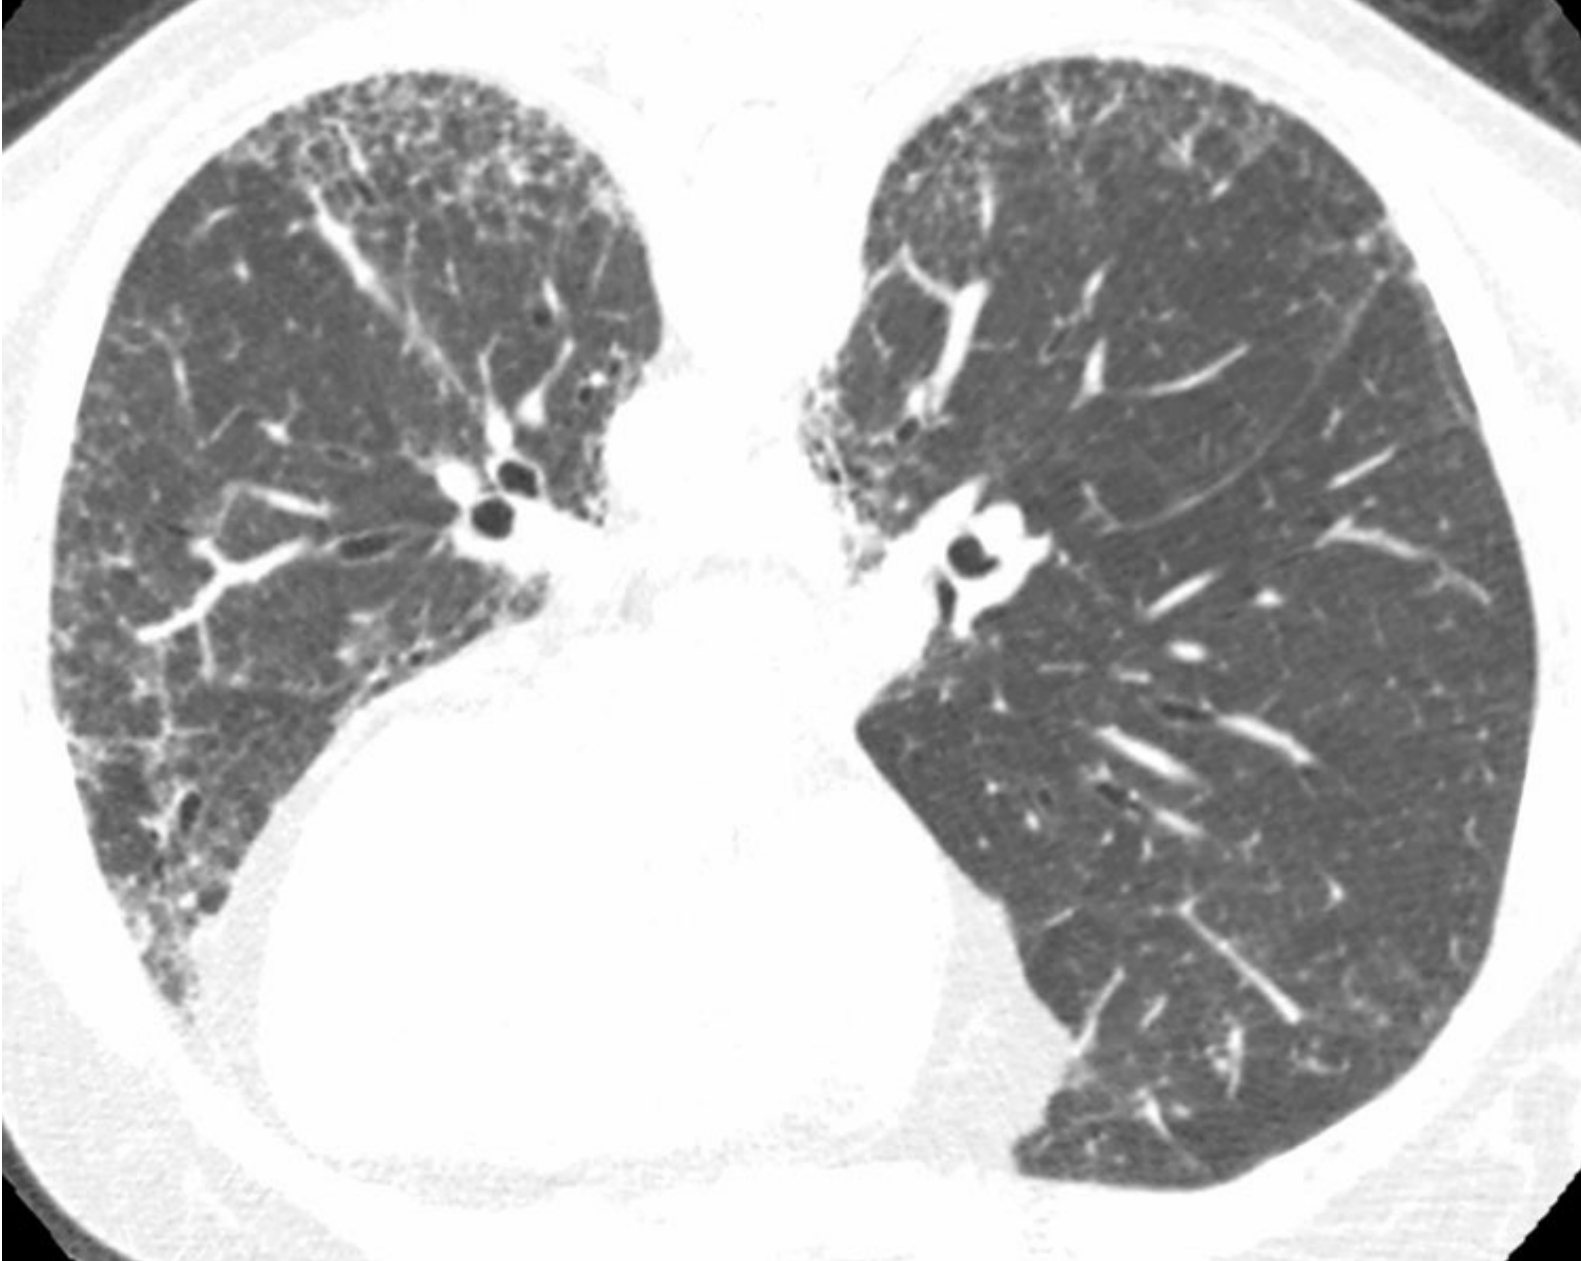

eb8e21eebff9ef7cc5bf91aa43df6ecf.png

炎症与纤维化的HRCT不同表现。

间质性肺炎表现为不同程度的炎症和纤维化;A和B. 2例结缔组织病患者的非特异性间质性肺炎。

A.HRCT显示GGO,无明显的纤维化征象,提示潜在可逆的炎症性病变;

B.HRCT显示牵拉性支气管扩张(箭)及不规则网状影的纤维化征象,提示对治疗不敏感的肺部瘢痕。